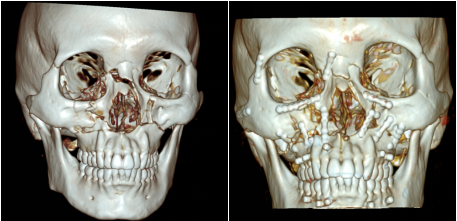

我院神经外科接收患者入院后,立即进行上下颌骨 CT 平扫及三维重建,结果显示:双侧上颌骨、颧弓、颧骨、鼻骨多发粉碎性骨折。神经外科紧急联系口腔科会诊,口腔科医生对患者严重的颅颌面伤情进行了细致检查,鉴于患者病情,建议待专科病情平稳后转至口腔科进行面部多发性粉碎性骨折手术治疗。

患者脑外伤病情趋于稳定转入口腔科后。口腔科周翊飞主任团队对其进行了全面的术前评估。考虑到患者存在双侧上颌骨、颧弓、颧骨、鼻骨多发粉碎性骨折,尤其是上颌为LefortⅠ型骨折,致使上颌牙弓下沉,咬合关系紊乱。这一情况不仅影响面部美观,还导致咀嚼功能完全丧失,无法经口正常进食。由于粉碎性骨折手术复位难度极高,团队决定采用数字化外科技术辅助设计并拼接骨折断端,模拟重建咬合关系并 3D 打印咬合导板,以此辅助颌面部多发性粉碎性骨折复位固定。

术前CT(三维成像)

术前术后CT对比